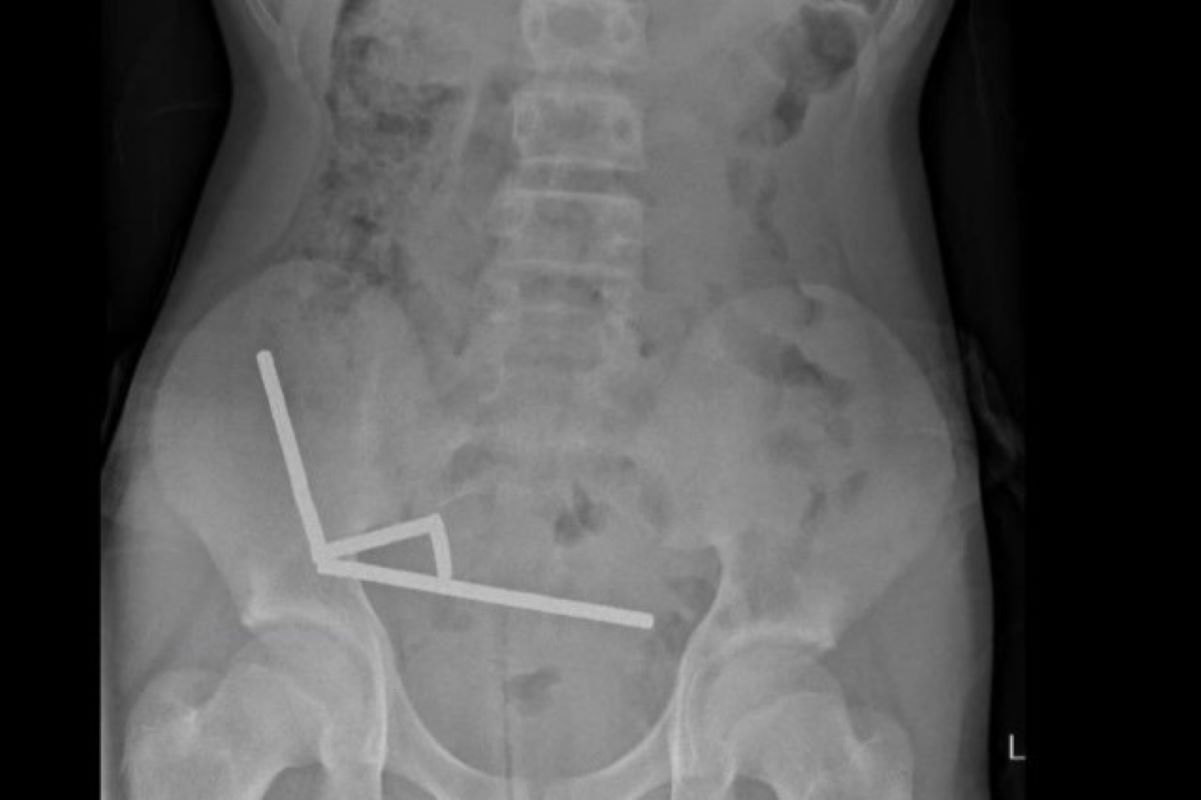

O intestino do adolescente sofreu necrose por pressão causada pela atração magnética dos ímãs, o que levou à perda de parte do órgão